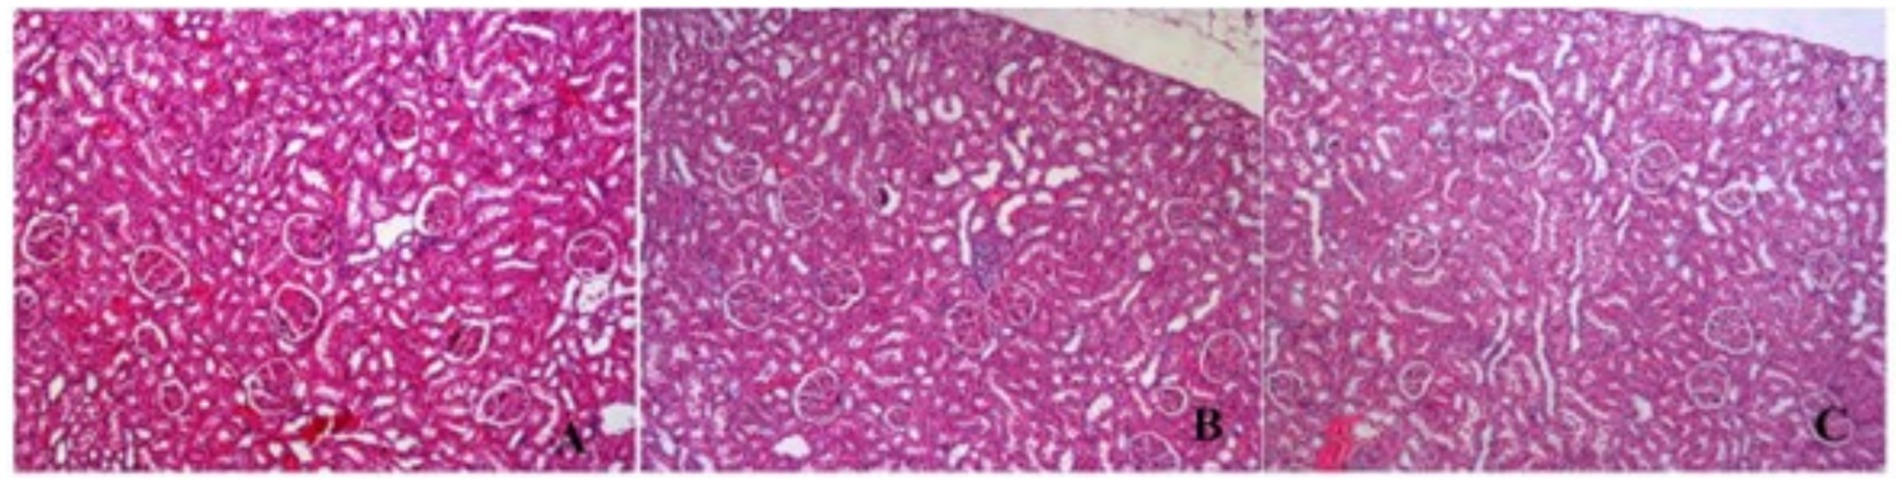

In kidneys, no findings were observed except congestion, mild interstitial inflammation and hyaline casts in some tubules (Figures 9, 10).

Figure 9. H&E section in kidneys samples congestion, mild interstitial inflammation and hyaline casts in some tubules. (A) Control (H&E X100) (B) P/E: Proestrus/Estrus phase, (H&E X100) (C) D/M: Diestrus/Metestrus phase. (H&E X100).

In liver samples from the control and G. glabra groups, mild sinusoidal dilatation, congestion, and mild portal inflammation in some samples were observed, but this was not significant. In the kidneys, no findings were observed other than congestion, mild interstitial inflammation, and hyaline casts in some tubules. Consequently, upon histopathological examination of liver and kidney tissues, no significant differences were observed in licorice-treated liver and kidney tissue samples compared to control. However, glycyrrhizin, the main saponin component of licorice, and its metabolites have previously been associated with mineralocorticoid-like effects and electrolyte imbalances, indicating a potential toxicity profile (34). Therefore, close monitoring of hepatic and renal parameters is essential in studies involving long-term or high-dose licorice consumption.